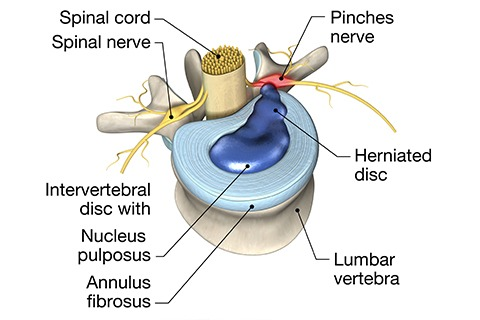

A herniated disc, also known as a slipped or ruptured disc, occurs when the soft inner gel-like substance of the spinal disc (nucleus pulposus) leaks out through a tear in the tough outer layer (annulus fibrosus). This condition can cause pain, numbness, or weakness in the spine and areas where the affected nerves travel.

Spinal discs are cushion-like pads located between the vertebrae in the spine. Each disc acts as a shock absorber, allowing for flexibility and movement while protecting the vertebrae from impact. The disc has two main parts:

- Nucleus Pulposus: The soft, jelly-like core that provides cushioning.

- Annulus Fibrosus: The tough, fibrous outer layer that encases and protects the nucleus pulposus.